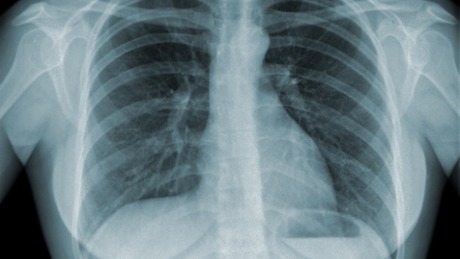

Number of TB cases in India may be higher than current estimates: Study

NEW DELHI: The number of tuberculosis cases in India may be up two to three times higher than current estimates, a new study has said while underlining the need for strengthening the surveillance of the disease.

Terming tuberculosis as a major global public health challenge, the study said that in 2014, 6.3 million cases of tuberculosis worldwide were reported to WHO, with India accounting for over a quarter of these cases, the highest of any country.